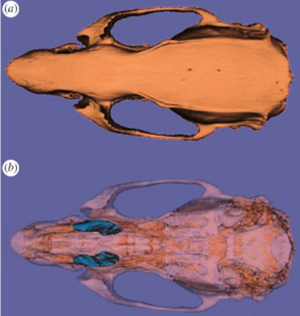

A Novel Procedure for Rapid Imaging of Adult Mouse Brains with MicroCT using Iodine-Based Contrast

Publication: PLoS One. 2015 Nov 16;10(11):e0142974. PMID: 26571123 | PDF Authors: Anderson R, Maga AM. Institution: Center for Developmental Biology and Regenerative Medicine, Seattle Children's Research Institute, Seattle, WA, USA. Background/Purpose: High-resolution Magnetic Resonance Imaging (MRI) has been the primary modality for obtaining 3D cross-sectional anatomical information in animals for soft tissue, particularly brain. However, costs associated with MRI can be considerably high for large phenotypic screens for gross differences in the structure of the brain due to pathology and/or experimental manipulations. MicroCT (mCT), especially benchtop mCT, is becoming a common laboratory equipment with throughput rates equal or faster than any form of high-resolution MRI at lower costs. Here we explore adapting previously developed contrast based mCT to image adult mouse brains in-situ. We show that 2% weight per volume (w/v) iodine-potassium iodide solution can be successfully used to image adult mouse brains within 48 hours post-mortem when a structural support matrix is used. We demonstrate that hydrogel can be effectively used as a perfusant which limits the tissue shrinkage due to iodine. Funding:

A. A representative high-resolution MRI scan of an age matched C57BL/6J displaying the brain and the mCT overlay (yellow outline) from [21]. B. Equivalent cross sections from five females that constitute the Group A (Hg perfusion) after 48h of staining in 2% I2KI. C. One individual that constitutes Group B (PFA perfusion) after 48h of staining in 2% I2KI. D-F: Heatmaps showing the difference in the obtained segmentations with respect to the reference MRI atlas constructed from [21,22]. To remove volumetric differences due to sex and age, we isometrically scaled our segmented brains to match the volume of the reference MRI atlas. Root mean square (RMS) errors are calculated after the scaling. D: Comparison of our Group A mCT atlas. RMS = 0.128 mm. E: Comparison of individuals of Group A. RMS values are 0.172 mm, 0.143 mm, 0.156 mm, 0.142 mm, 0.196 mm respectively. F: Comparison of Group B. RMS = 0.232 mm. All comparisons are rendered on MRI reference atlas. Grey areas in the heat map indicate regions of large difference (>0.5 mm) either due to extreme shrinkage or difference in segmentation. Using this outline as the boundary, stained brains were interactively segmented using the editor module of 3D Slicer. |